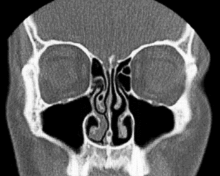

Normal Nose CT Front cross section

Coronal section of nasal cavities.